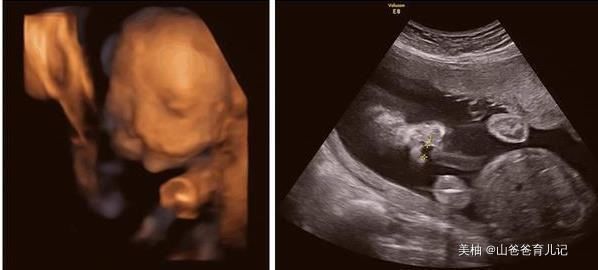

小郭因为是第一次怀孕,和老公来到医院做了B超检查后,竟然是两个孩子,以为那肯定就是双胞胎,高高兴兴的回家了,并且将这个喜讯告诉了家里人,婆婆听说后,更是激动的第二天就从乡下过来照顾小郭。

但是手术并不顺利,小郭进去了很长时间,全家人也等的十分焦急,开始的激动心情变得忐忑不安,结果孩子生出来时候,全家乱成一团,确实是两个孩子,但却是连体婴儿,如果做手术,两个孩子将面临很大的风险,还要面对高昂的手术费。